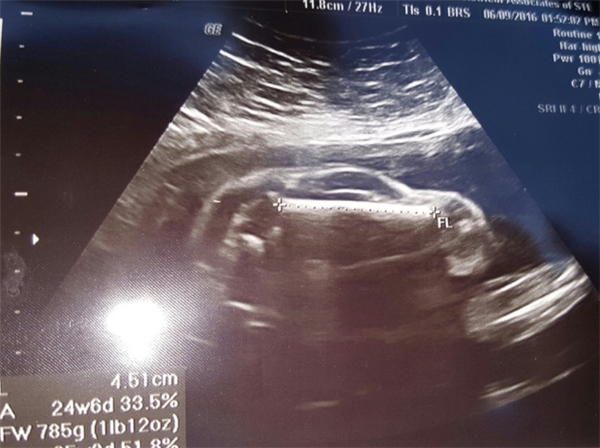

Old  Default Kinh hoàng khi đi siêu âm thấy cả xe hơi trong bụng

Trước nay đã có nhiều hình ảnh siêu âm “dị thường” được cộng đồng mạng truyền tay nhau. Lần này, lại thêm một hình ảnh siêu âm nữa sẽ khiến bạn phải há hốc miệng khi xem. Có thể nhìn thấy rõ một chiếc xe hơi trong bụng của 1 thai phụ qua tấm hình này.

Mới đây, một người dùng mạng với biệt danh Brewhaus3223 đã đăng tải tấm ảnh được cho là hình siêu âm đứa con thứ hai của anh chàng lên trang xã hội có tiếng Reddit. Với lời giới thiệu hài hước: "Vợ tôi đang mang bầu xe hơi thể thao đó", cư dân mạng ngay lập tức chú ý ngay đến cái bóng mờ đáng kinh ngạc trong bức hình. Và rồi, mọi người như vỡ oà: "Thánh thần ơi, quả thật là chiếc xe hơi"...

Và rồi, như em sóng biển được tiếp thêm sức mạnh từ anh gió lốc, cư dân mạng thế giới lan truyền tấm hình siêu âm "xe hơi" với một tốc độ chóng mặt. (Ảnh: Brewhaus3223)

Theo tờ Metro đưa tin, trước đó, hai vợ chồng đã có một đứa con gái nhờ công nghệ thụ tinh nhân tạo. Khi đứa đầu tiên được 6 tháng tuổi, người vợ lại mang thai lần nữa. "Phép lạ đã xảy ra khi việc mang thai lần 2 của vợ tôi là hoàn toàn tự nhiên, và lại càng kì diệu hơn nữa khi bạn mang hẳn một 'chiếc xe hơi' trong bụng", người cha chia sẻ.

Trước tất cả bình luận tỏ ra bất ngờ hay khen ngợi, hâm mộ hình ảnh siêu âm đứa con của hai vợ chồng, người cha này đã vô cùng phấn khích thông báo thêm rằng "đây là xe nam đấy".